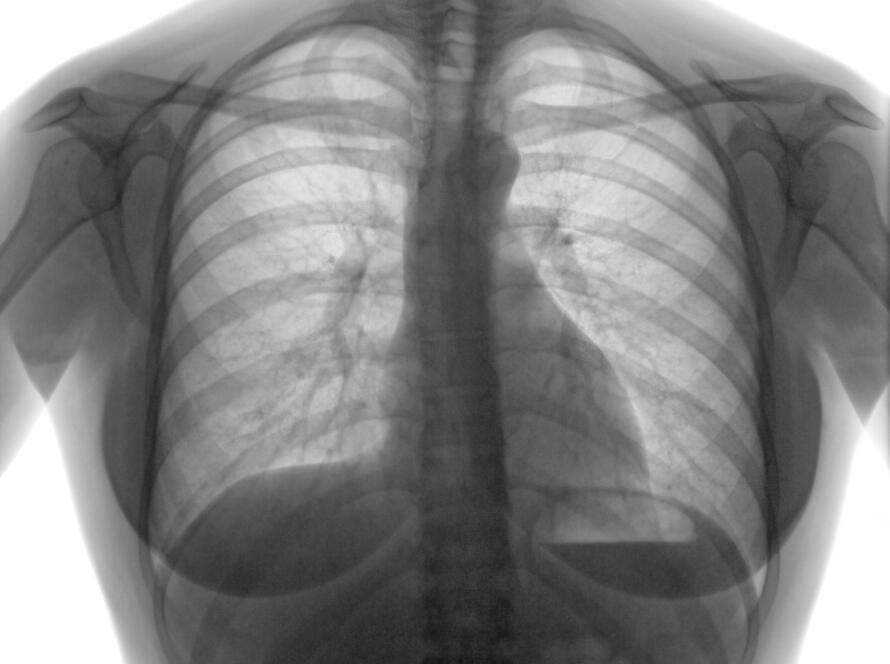

Dr. E. Halit Yardımcı, Yeditepe Üniversitesi Tıp Fakültesi’nden mezun olmuş, göğüs cerrahisi uzmanlık eğitimini Siyami Ersek Hastanesi’nde tamamlamıştır. Halen Marmara Üniversitesi bünyesinde akciğer kanseri ve mediasten hastalıkları başta olmak üzere göğüs cerrahisi alanındaki klinik ve akademik çalışmalarını sürdürmektedir.

Akciğer ve Mediasten Cerrahisinde İleri Yaklaşım

Akciğer kanseri ve mediasten tümörlerinin cerrahi tedavisinde, güncel bilimsel veriler doğrultusunda bireyselleştirilmiş bir yaklaşım benimsenmektedir. Minimal invaziv cerrahi teknikleri başta olmak üzere, modern cerrahi yöntemler kullanılarak hastalar için güvenli ve etkin tedavi seçenekleri sunulmaktadır.